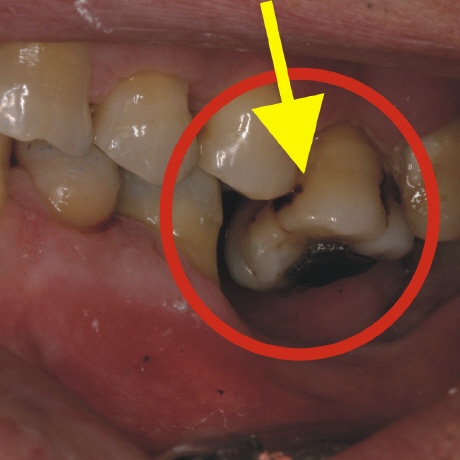

Das Bild oben läßt es leicht erahnen. Durch den herausgewachsenen Zahn (gelber Pfeil) sind massive Veränderungen im Kausystem enstanden. Bei Kau- bzw. Mahlbewegungen können die Zähne nicht mehr auf ihren dafür vorgesehenen Flächen gleiten, da der herausgewachsene Zahn das verhindert.